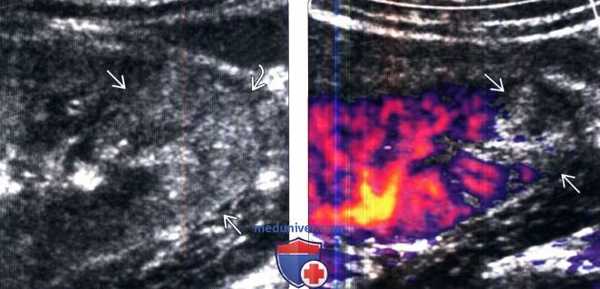

(Слева) УЗИ в режиме серой шкалы, сагиттальная плоскость сканирования: при остром геморрагическом пиелонефрите обнаружены клиновидные области повышенной эхогенности в нижнем полюсе и тонкий ободок прилежащей околопочечной жидкости.

(Справа) Энергетическая допплерография, сагиттальная плоскость сканирования: у данного пациента выявлено отсутствие потока в области пиелонефрита.